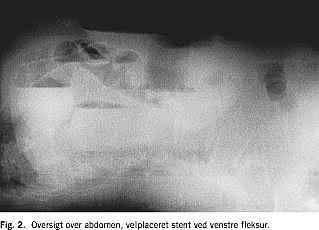

En 87-årig kvinde med kendt tidligere transitorisk cerebral iskæmi og velbehandlet myksødem blev henvist af egen læge til koloskopi pga. ca. et år varende tendens til træg afføring og anæmi. Ved koloskopien fandt man ca. 90 cm fra anus en malignt udseende stenotisk proces. En colonindhældning viste totalt stop ved venstre fleksur ( Fig. 1 ), supplerende undersøgelser viste ingen tegn på metastaser. Der blev anlagt selvekspanderende metalstent under gennemlysning. Der var umiddelbart efter proceduren luft- og fæcesafgang, og en kontrolrøntgen viste velekspanderet stent i det stenotiske colonsegment (Fig. 2 ). Seks dage efter blev der foretaget elektiv laparoskopisk venstresidig hemikolektomi og primær anastomose. Man fandt en tumor i venstre fleksur. Det postoperative forløb var ukompliceret, og patienten kunne udskrives i velbefindende og med tarmfunktion den syvende postoperative dag. En histologisk undersøgelse viste Dukes C adenokarcinom. En kontrolkoloskopi for clean colon viste normale forhold. Ved klinisk kontrol efter et år var patienten velbefindende, uden tegn på recidiv eller metastaser.